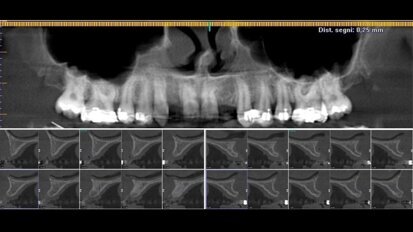

Arcate superiore e inferiore riabilitate con Chirurgia Guidata Simultanea full arch

Paziente donna di ottant’anni, presenta uno stato di salute ottimale, non assume farmaci. Dal punto di vista odontoiatrico chiede una riabilitazione delle...